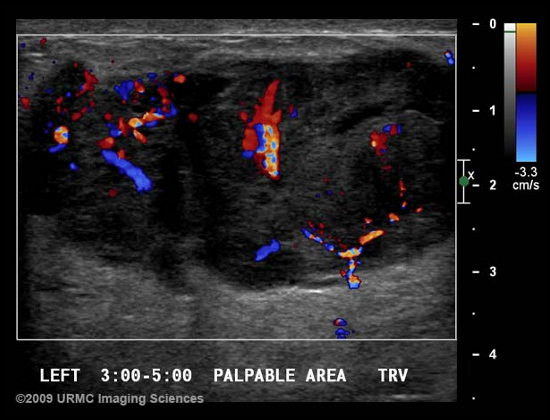

RDUS ile damar hastalıklarının araştırılması, doku ve organlardaki kan damarlarının dağılımının incelenmesi ve dolayısıyla tümörlerde kanserleşme eğilimlerinin araştırılması mümkündür. Memenin ve bölgenin incelenmesinde damarsal yapıların lezyonlarla ilişkisi ve damarlanması açısından yol gösterici olabilir.

Memede ele gelen kitle varlığında bu kitlenin ne olduğunun belirlenebilmesi için US inceleme yapılır. Bu kitlenin kist (sıvı keseciği) ya da solid (katı kitle) olup olmadığı değerlendirilir, yapısal özellikleri hakkında bilgi verir.